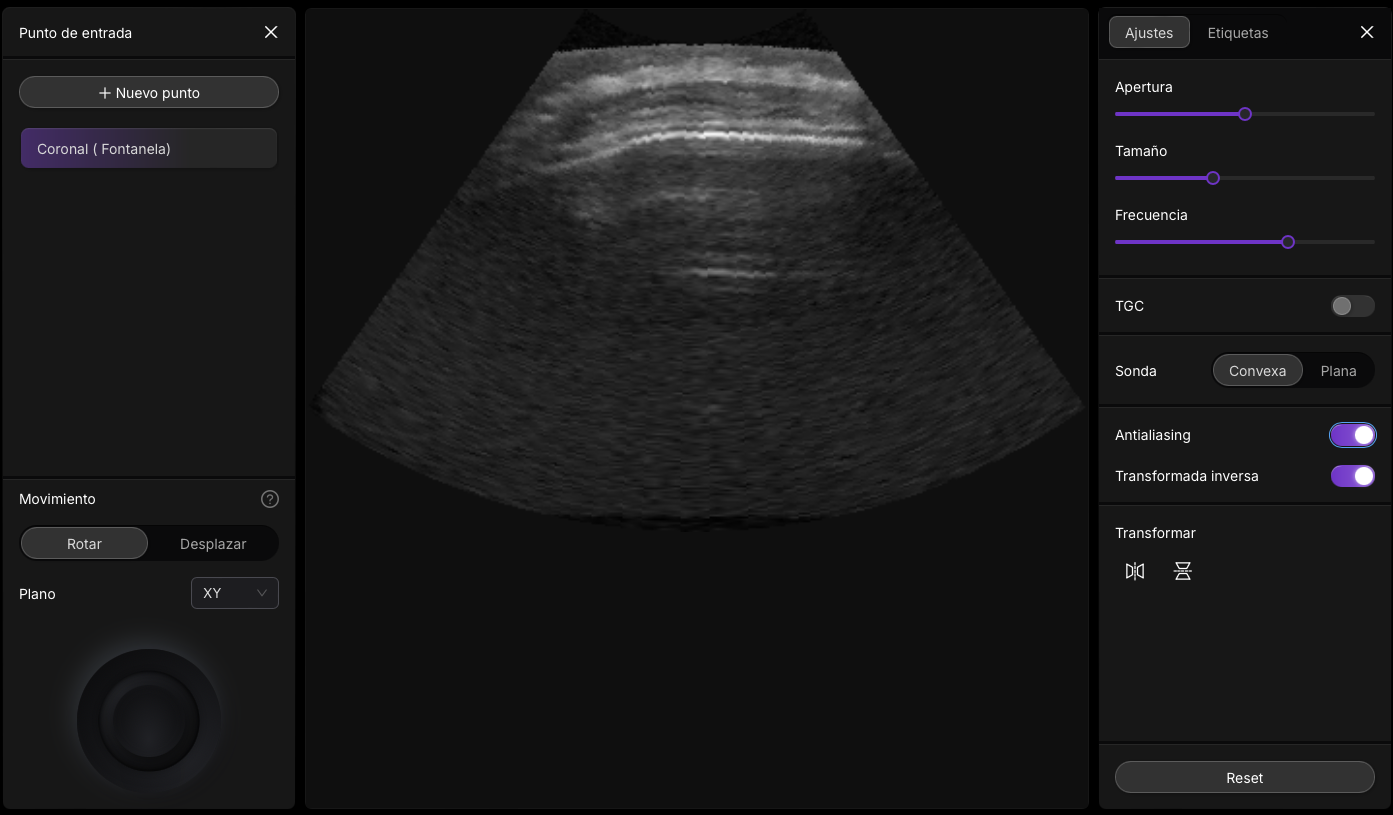

Accede al simulador interactivo docente

Simulador de Artefacto de refuerzo acústico

Simulador interactivo del artefacto de refuerzo acústico posterior

Simulación de adquisición de imágenes vesicales

Simulación de adquisición de imágenes vesicales con variaciones del refuerzo acústico según el ángulo de incidencia